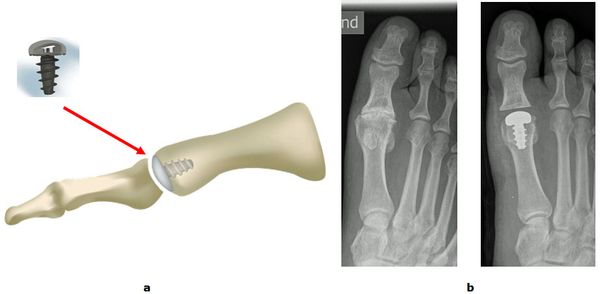

Abb.7: Implantation einer Endoprothese Typ Hemi CAP im Großzehengrundgelenk.

a Schema und Modell

b Röntgenbilder Vor und nach der Operation